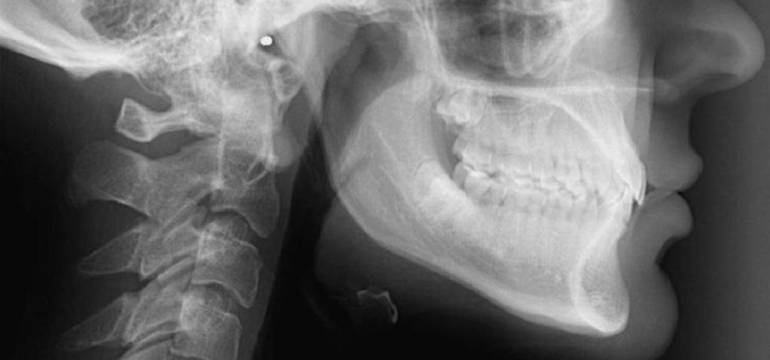

Cefalometria uznawana jest za jedną z odmian zewnątrzustnych zdjęć rentgenowskich, które mają swoje zastosowanie w stomatologii i implantologii. Wykonywana jest ona w trzech projekcjach. Pierwszą z nich jest ta boczna, drugą tylno-przednia, a trzecią osiowa. Najczęściej jednak dokonuje się badania metodą pierwszą – od boku. Celem badania cefalometrycznego  jest zaś obrazowanie struktury czaszki, tkanek miękkich i twardych jamy ustnej, podniebienia twardego, a także zatok przynosowych. Warto przy tym wiedzieć, że niekiedy ma ona swoje zastosowanie w chirurgii, również po przebytych ciężkich wypadkach głowy, czy szczęki.

Cefalometria ma szczególne zastosowanie przy diagnostyce wad zgryzu oraz wad rozwojowych części twarzowej czaski. Pozwala ona zatem planować leczenie ortodontyczne, czy to, które należy wykonać po wypadkach. Cefalometria umożliwia bowiem badać procesy rozwoju i rozrostu szczęki oraz czaski, czy nawet pozwala oceniać wiek kostny. Dzięki temu rodzajowi badań/zdjęć można dowolnie dokonywać pomiarów punktów, odległości, linii i kątów w obrębie kości twarzy.